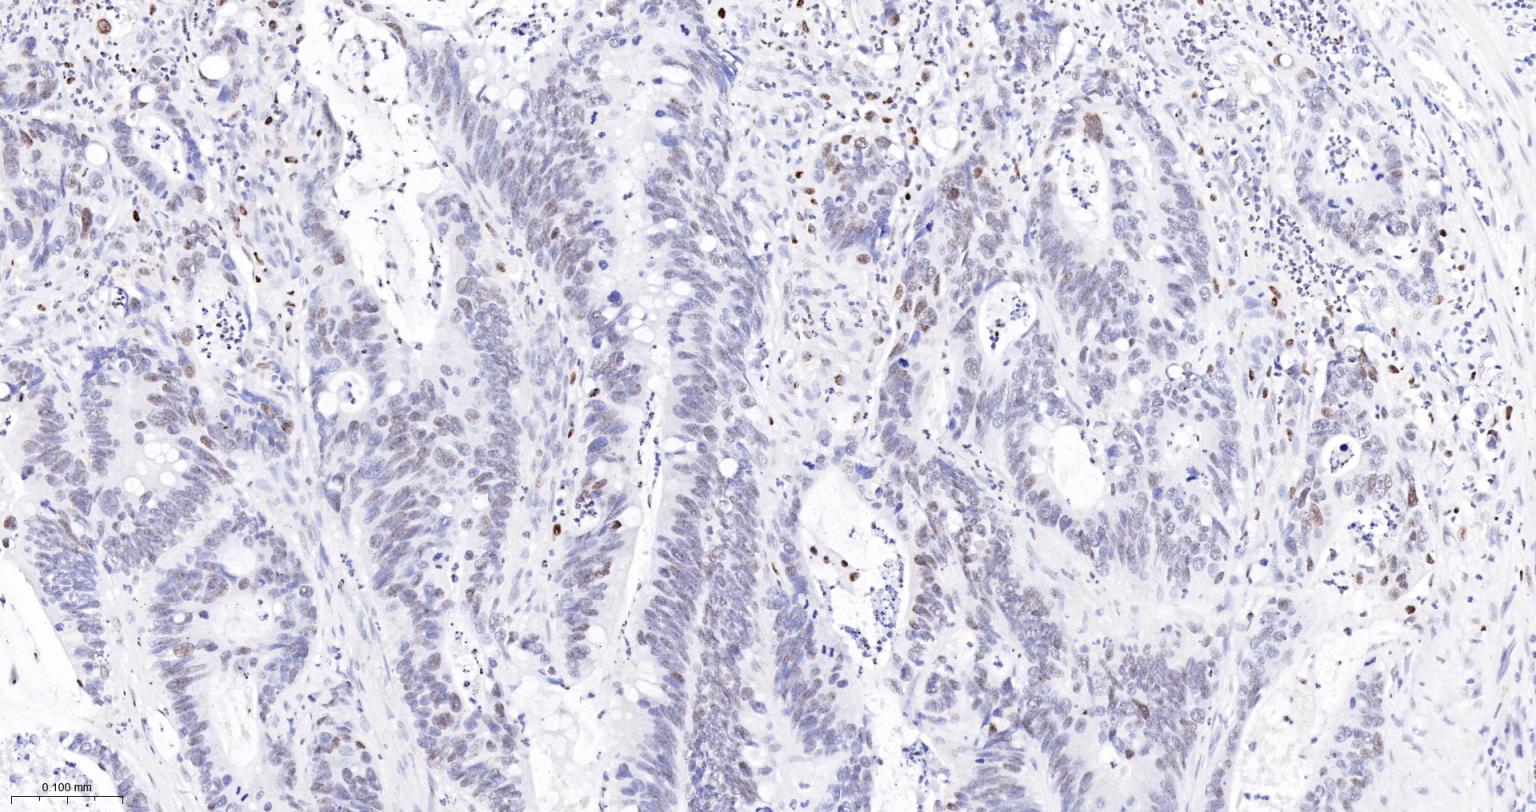

Paraformaldehyde-fixed, paraffin embedded Human Endometrial Cancer; Antigen retrieval by boiling in sodium citrate buffer (pH6.0) for 15 min; The section was incubated with PB1 Monoclonal Antibody, Unconjugated (bsm-61815R) at 1:200 overnight at 4°C, followed by conjugation to the bs-0295G-HRP and DAB (C-0010) staining.